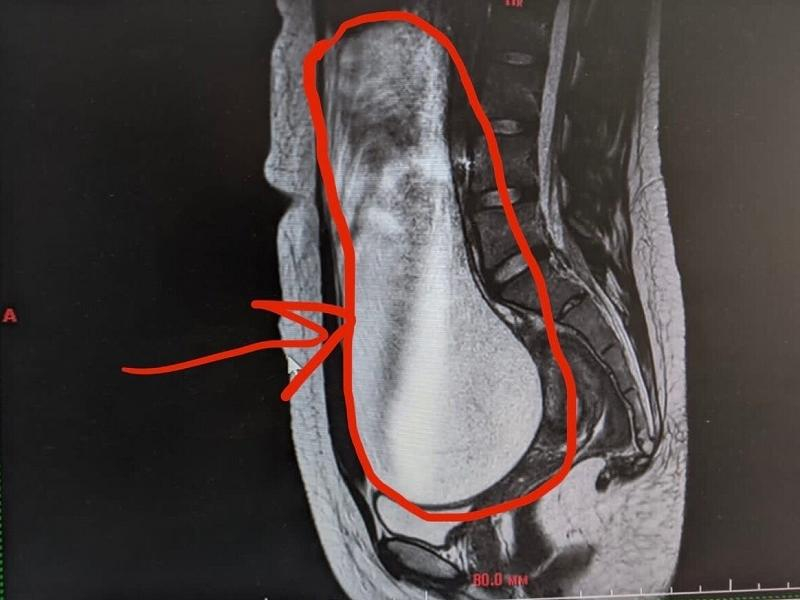

В стационаре девочке провели МРТ с контрастным усилением, и нашли кистозное образование правых придатков матки объемом около трех литров, которое занимало практически всю брюшную полость и сдавливало внутренние органы: мочеточники, мочевой пузырь, петли кишечника. Хирурги решили немедленно оперировать.

– Удаление образования было необходимо в связи с тем, что оно могло и дальше увеличиваться в размерах, продолжая сдавливать органы и сосуды, – рассказал заведующий общехирургическим отделением, детский хирург Антон Морозов.